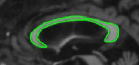

InitializationConverged ContourRefer to captionRefer to captionRefer to captionRefer to captionInitializationConverged ContourRefer to captionRefer to captionRefer to captionRefer to caption\begin{array}[]{cc}\mbox{Initialization}&\mbox{Converged Contour}\\ \includegraphics[width=112.0187pt]{rethina1_init.pdf}&\includegraphics[width=112.0187pt]{rethina_result_1.pdf}\\ \includegraphics[width=112.0187pt]{img008Init.pdf}&\includegraphics[width=112.0187pt]{img008.pdf}\\ \end{array}

Figure 8: Results on fundus images: Left column shows initialization and right column shows the converged contour.

5.3 Elliptical templates

Many of the bio-medical cells can be approximated with an ellipse [14]. We present results using two elliptical shaped templates: a spline synthesized ellipse for which we use the partial derivatives given in equations (36) and (41) directly, an exact ellipse for which we use the parameterization given in [16] and use the equation (26). First row of Figure 8 corresponds to a hand drawn ellipse and the second row correspond to a parametric ellipse. We considered these two parameterizations to show that the algorithm performance is not critically dependent on the parameterization. These are fundus images taken from [32]. The presence of veins in the fundus anatomy obscures snakes whose energies rely on image derivative functions. From the results shown in Figure 8, we infer that the proposed technique is less affected by the vein structures or the parameterization and captures the near elliptical shape of the fundus outline.